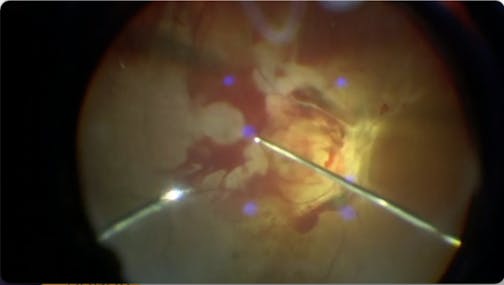

Myopic Macular Hole

Jose Garcia Arumi, MD

High Myopia and Macular Hole

Patricia Udaondo, MD

Myopic Macularschisis

Ehab El Rayes, MD